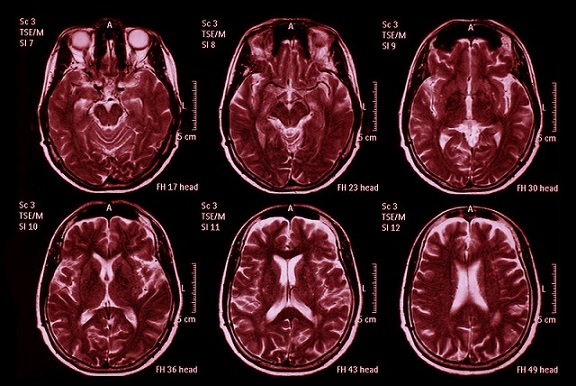

New MRI evidence shows that lasting brain tissue loss may explain persistent fatigue in people recovering

from severe COVID-19

Using advanced MRI scans, the team examined 57 patients who had been hospitalized for COVID-19 and compared them with 57 healthy individuals. Three months after these patients left the hospital, researchers discovered clear reductions in cortical thickness — especially in the parahippocampal gyrus, temporal lobes, and parts of the frontal cortex. These regions help manage memory, sensory processing, emotional regulation, and energy perception.

The study also found that both the left and right hippocampus were smaller in COVID survivors. On the scans shown in the study images, the shrinking of these structures was visually striking, indicating that the virus or its inflammatory aftermath may have caused lasting tissue injury. Patients with the most severe infections, including those who required mechanical ventilation, also had reduced thalamus volume, a part of the brain that handles alertness and information flow.